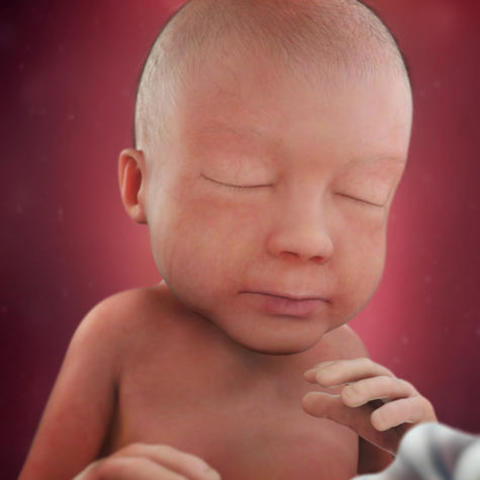

• birth

birth

a mother due date marks at the end of 40 weeks it calculates using the first day of her last period based on the pregnancy between 38 weeks and 42 weeks.